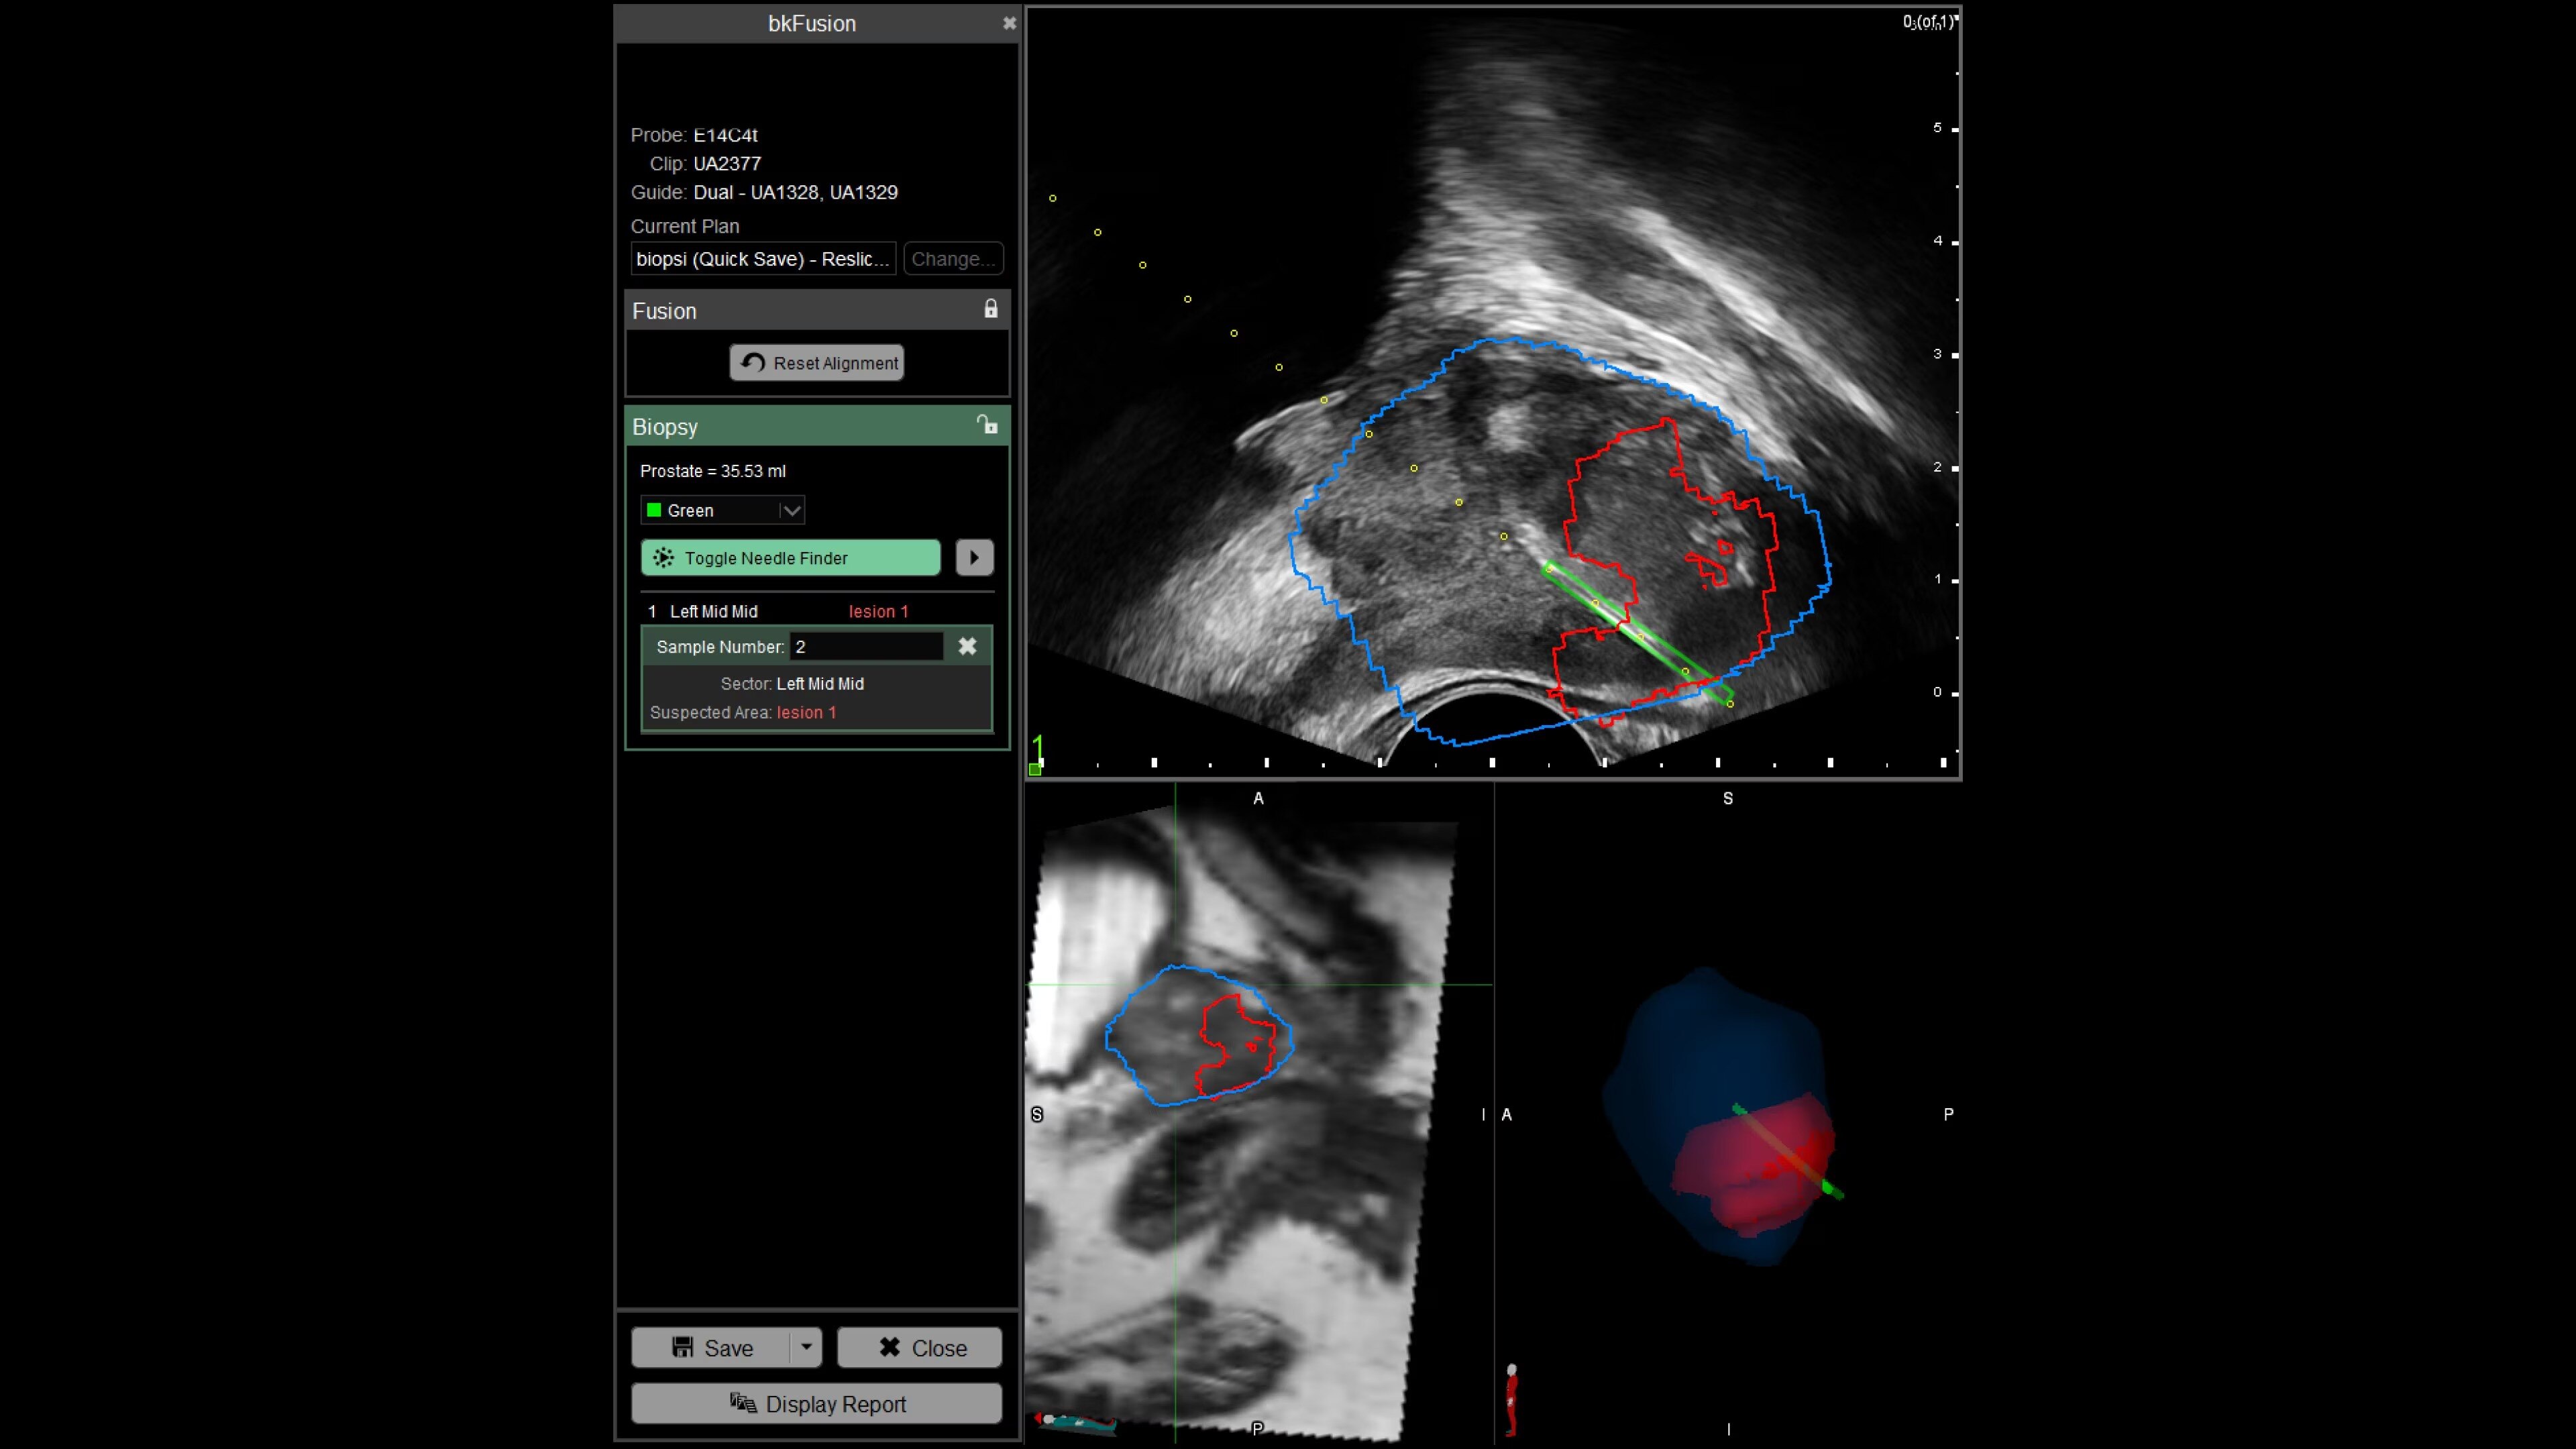

With bkFusion, confidently target your biopsy with clear visualization of organ borders to detect registration errors or deformations in real-time. bkFusion, MRI-ultrasound fusion biopsy solution features proprietary imaging algorithms developed with high spatial, temporal, and contrast resolution for advanced visualization.

bkFusion has proven to accurately detect 84% of PIRADS 3-5 lesions and up to 81% GG>=2 cancer.¹

Predictive Fusion®

Enhance biopsy accuracy with Predictive Fusion®

Predictive Fusion® is the proprietary registration method allowing you to imediately see any errors in the overly of MRI and ultrasound images before and during the procedure. Utilizing rigid 2D slice registration, it eliminates distortion in merging 3D shapes, ensuring precise MRI-ultrasound fusion. If changes are needed, make simple, one-touch, micro-adjustments to updte the registration without calibration steps or 3D sweeps. Enhance your prostate biopsy accuracy with this advanced technology.